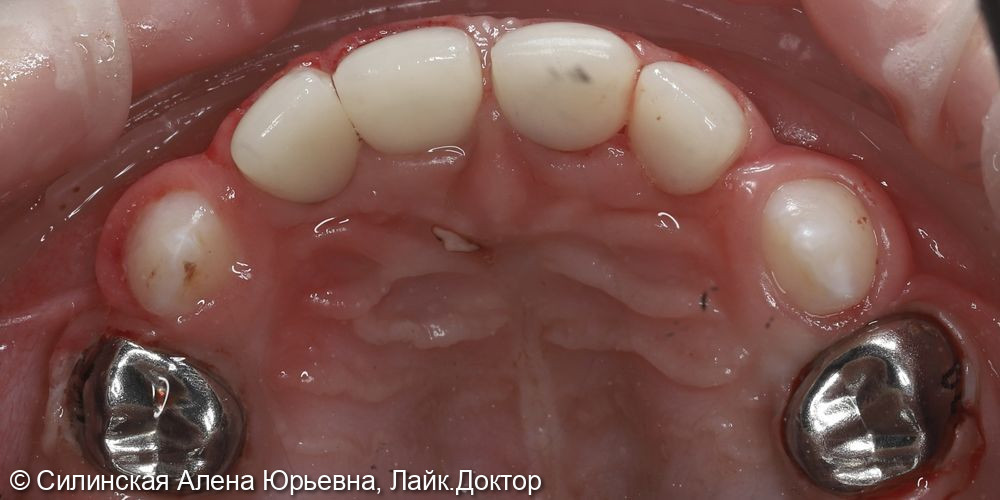

с использованием микроскопа под аппликационной анестезией геля «Benzocaini 20%»; проводниковой анестезией «Articaini 4%» 1:100000 очищение мягкого зубного налета, изоляция коффердам проведено препарирование кариозной (ых) полости (ей), под контролем витального окрашивания «Кариес Маркер» удалены деминерализованные участки эмали и дентина,Показать полностью...

85;84;75 : в условиях общего обезболивания: очищение мягкого зубного налета, изоляция коффердам,Показать полностью...